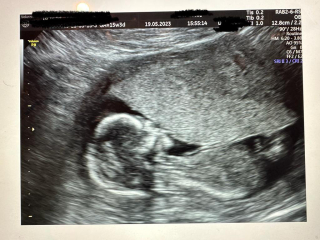

Not that it matters, I'm just wondering, do you think this but I've circled in pink is the fibroid? At 12 weeks it measured 3.5cm and if what I've circled is the fibroid it looks like it's not got bigger, which would be good. The doctor didn't mention it at all today as Prof A is looking properly next week.

@seven201 Thank you. How awful to have got all those bugs at once! Thanks for the tip, that's good to know - I've been checking my temp and it's ok. I'm glad your scan went well yesterday - such lovely photos! I don't know anything about fibroids, but what you've circled does look like it could be it - if so, glad it hasn't got any bigger and all is well x

@seven201 gorgeous pics! Sorry - I just looked and the fibroid and didn't notice the baby!! Congrats

@seven201 I'm not sure about the fibroid, but looks like it's quite far out, it's in the muscle I take it?